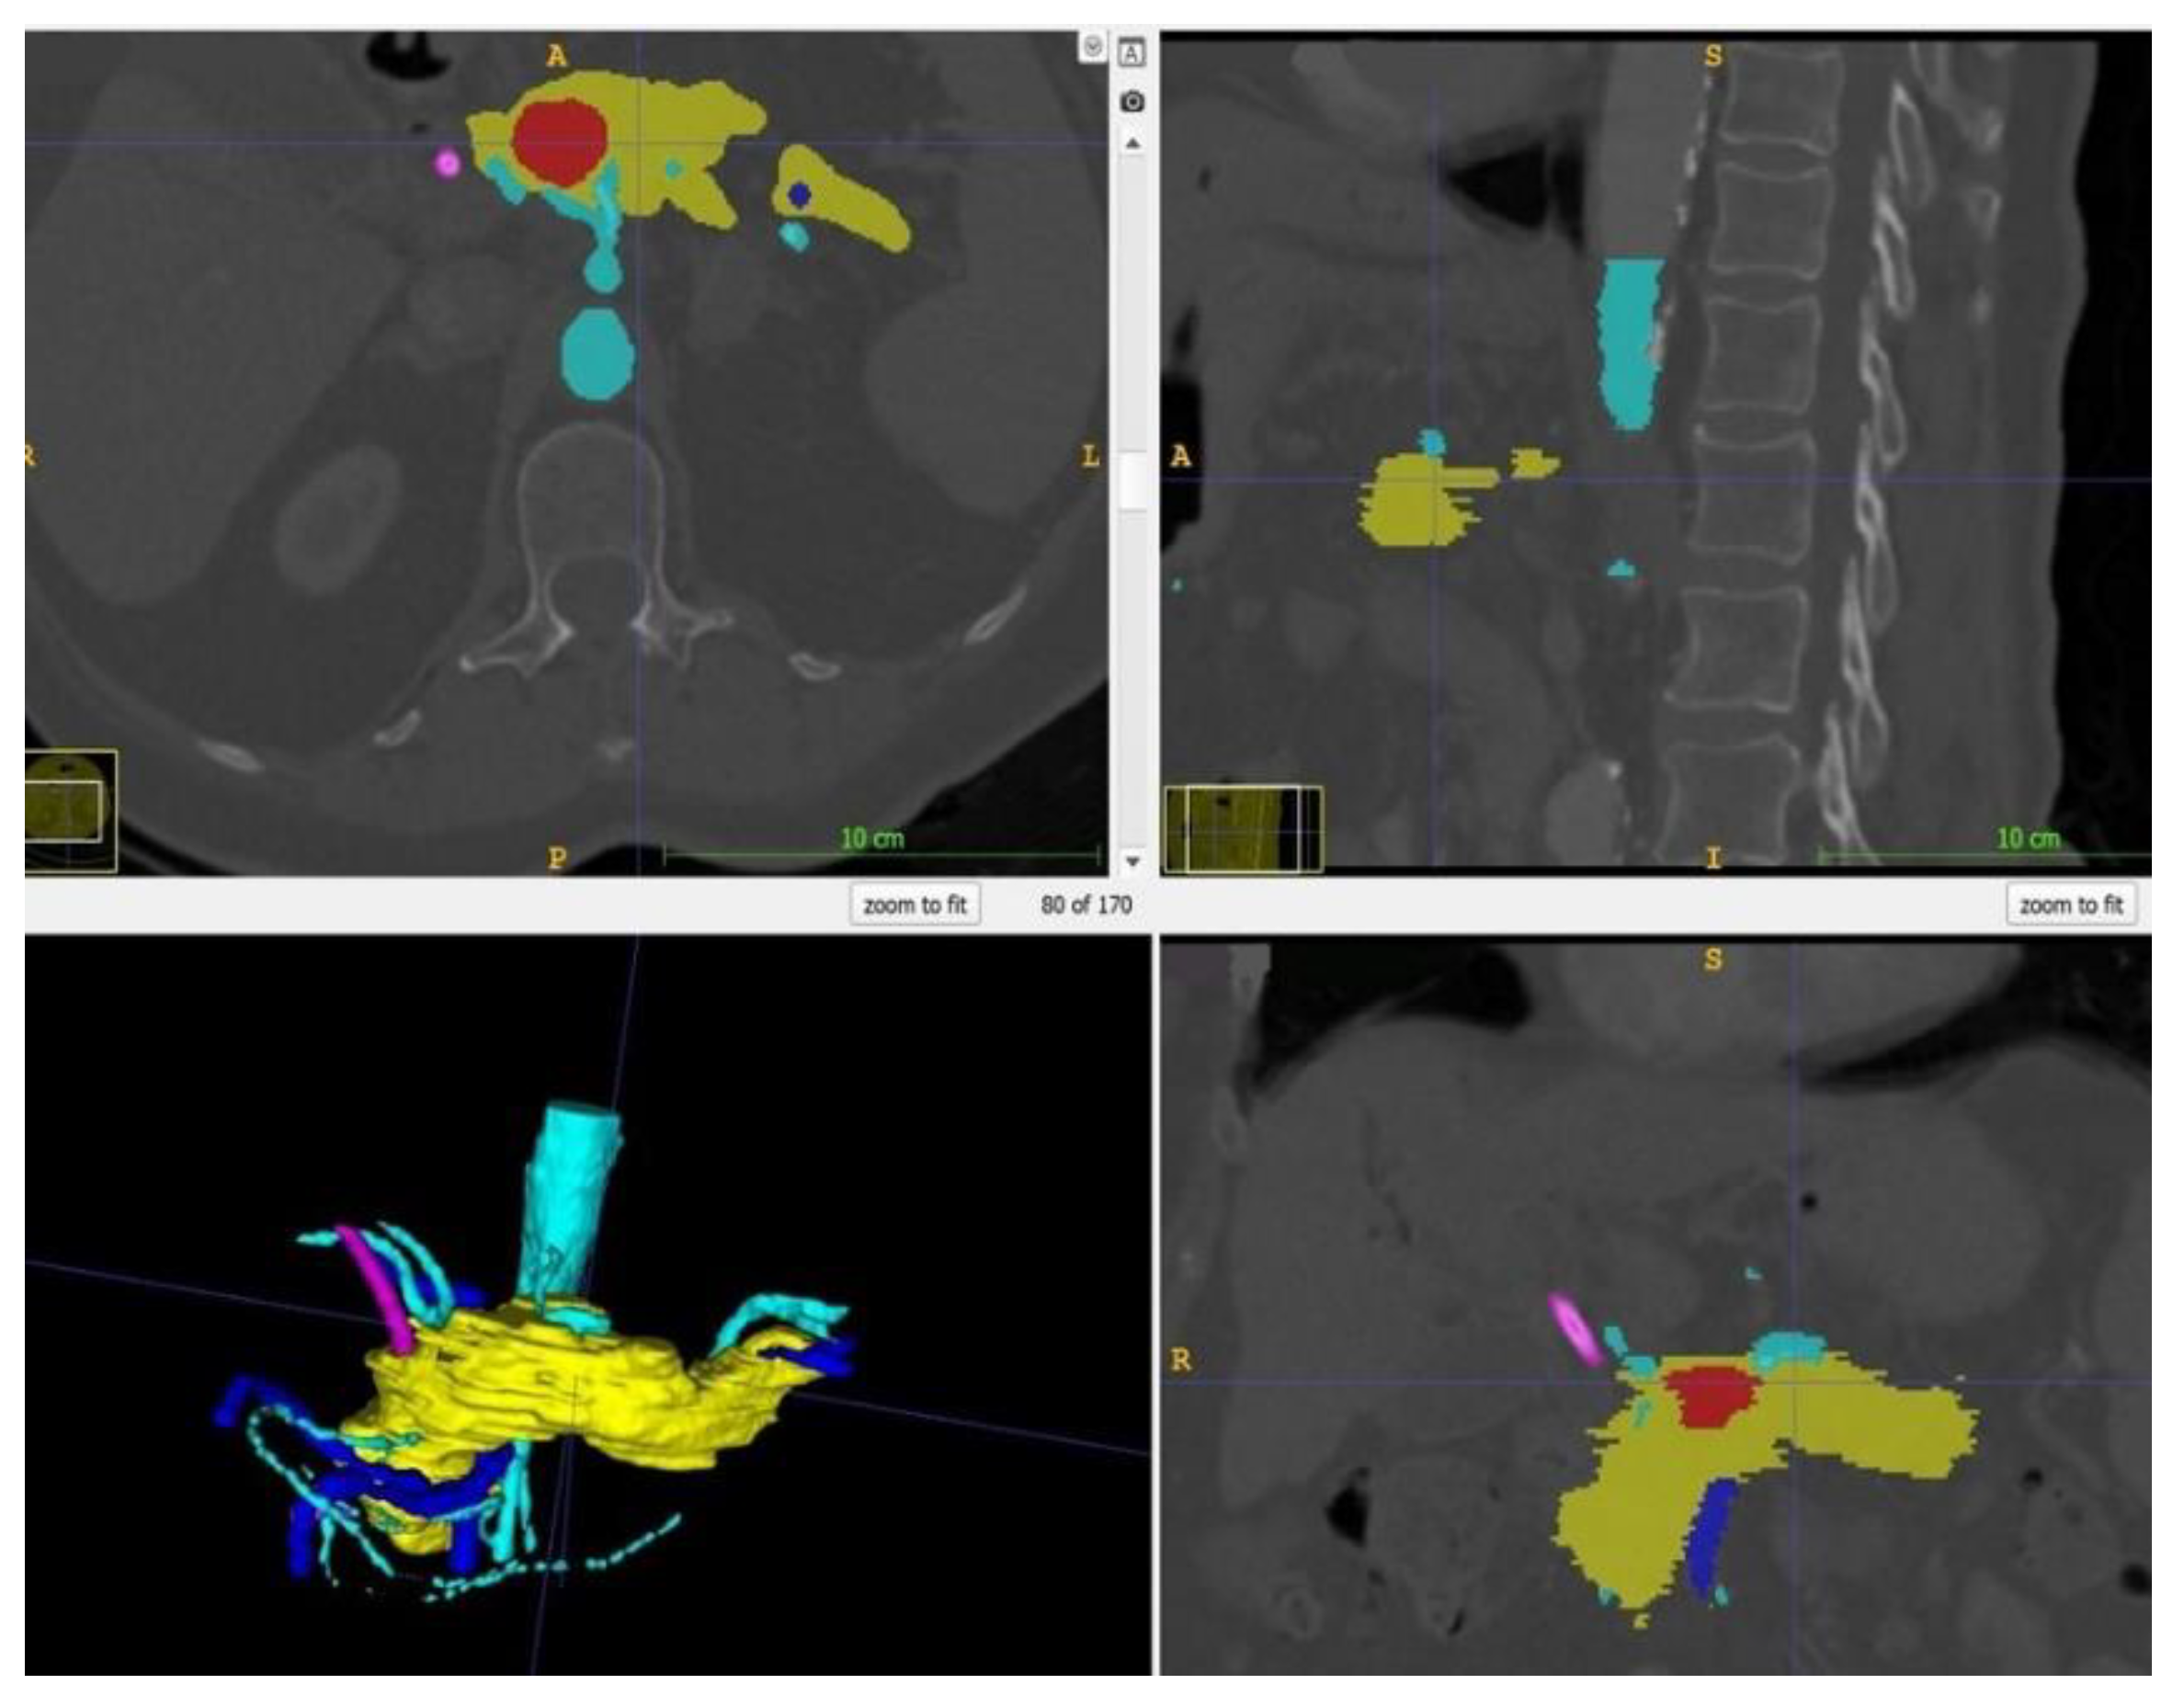

Within ITK Snap, the relevant structures, i.e., in this case the stomach, the pancreas, the tumor and the arteries and veins, were marked on each slide with different colors. Then, a 3D mesh was made from the 2D layer data (Step 2.b). The different meshes were exported as STL files. Figure 2 displays a screenshot of ITK Snap and Figure 3 demonstrates views from different angles on the created meshes.

Figure 2.

Screenshot of ITK Snap with the tumor in red, the pancreas in yellow, the arteries in light blue, the veins in dark blue and the splint in pink.